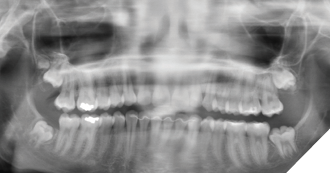

The patient was seen again 1 year following for radiologic reassessment and remained asymptomatic. The maxillary third molars were noted to have descended relative to the primary assessment, with increased mineralization of the maxillary supernumerary tooth (Fig. 2).

Fig. 2